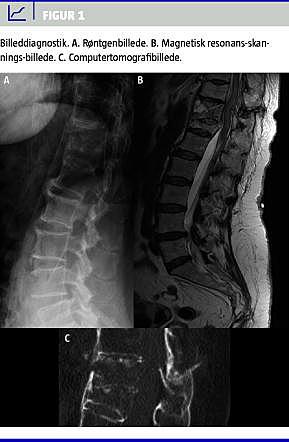

En 59-årig kvinde med paranoid skizofreni blev henvist til skadestuen, fordi hun fire dage tidligere var faldet og havde slået ryggen. Den kliniske undersøgelse viste let direkte, men ingen indirekte ømhed af columna. Sensorium og motorik var intakt. Et røntgenbillede gav ikke umiddelbart mistanke om fraktur (Figur 1 ), og patienten blev derfor overflyttet til psykiatrisk afdeling, hvorfra hun hurtigt blev udskrevet. På røntgenkonferencen dagen efter opdagede man en mindre kompressionsfraktur af Th12. Man forsøgte uden held at ringe til patienten og endte med at måtte sende et brev, hvori man beskrev fundet og anbefalede patienten at søge egen læge ved forværring eller manglende bedring.

Patienten blev straks sat i behandling med tinzaparin for lungeemboli, og der blev anlagt kateter à demeure og udtømt 2.500 ml urin. En efterfølgende computertomografi (CT) viste bilateral lungeemboli, ustabil fraktur i Th11, kompression af Th12 og medullær påvirkning (Figur 1). Patienten blev umiddelbart herefter overflyttet til et intensivafsnit.